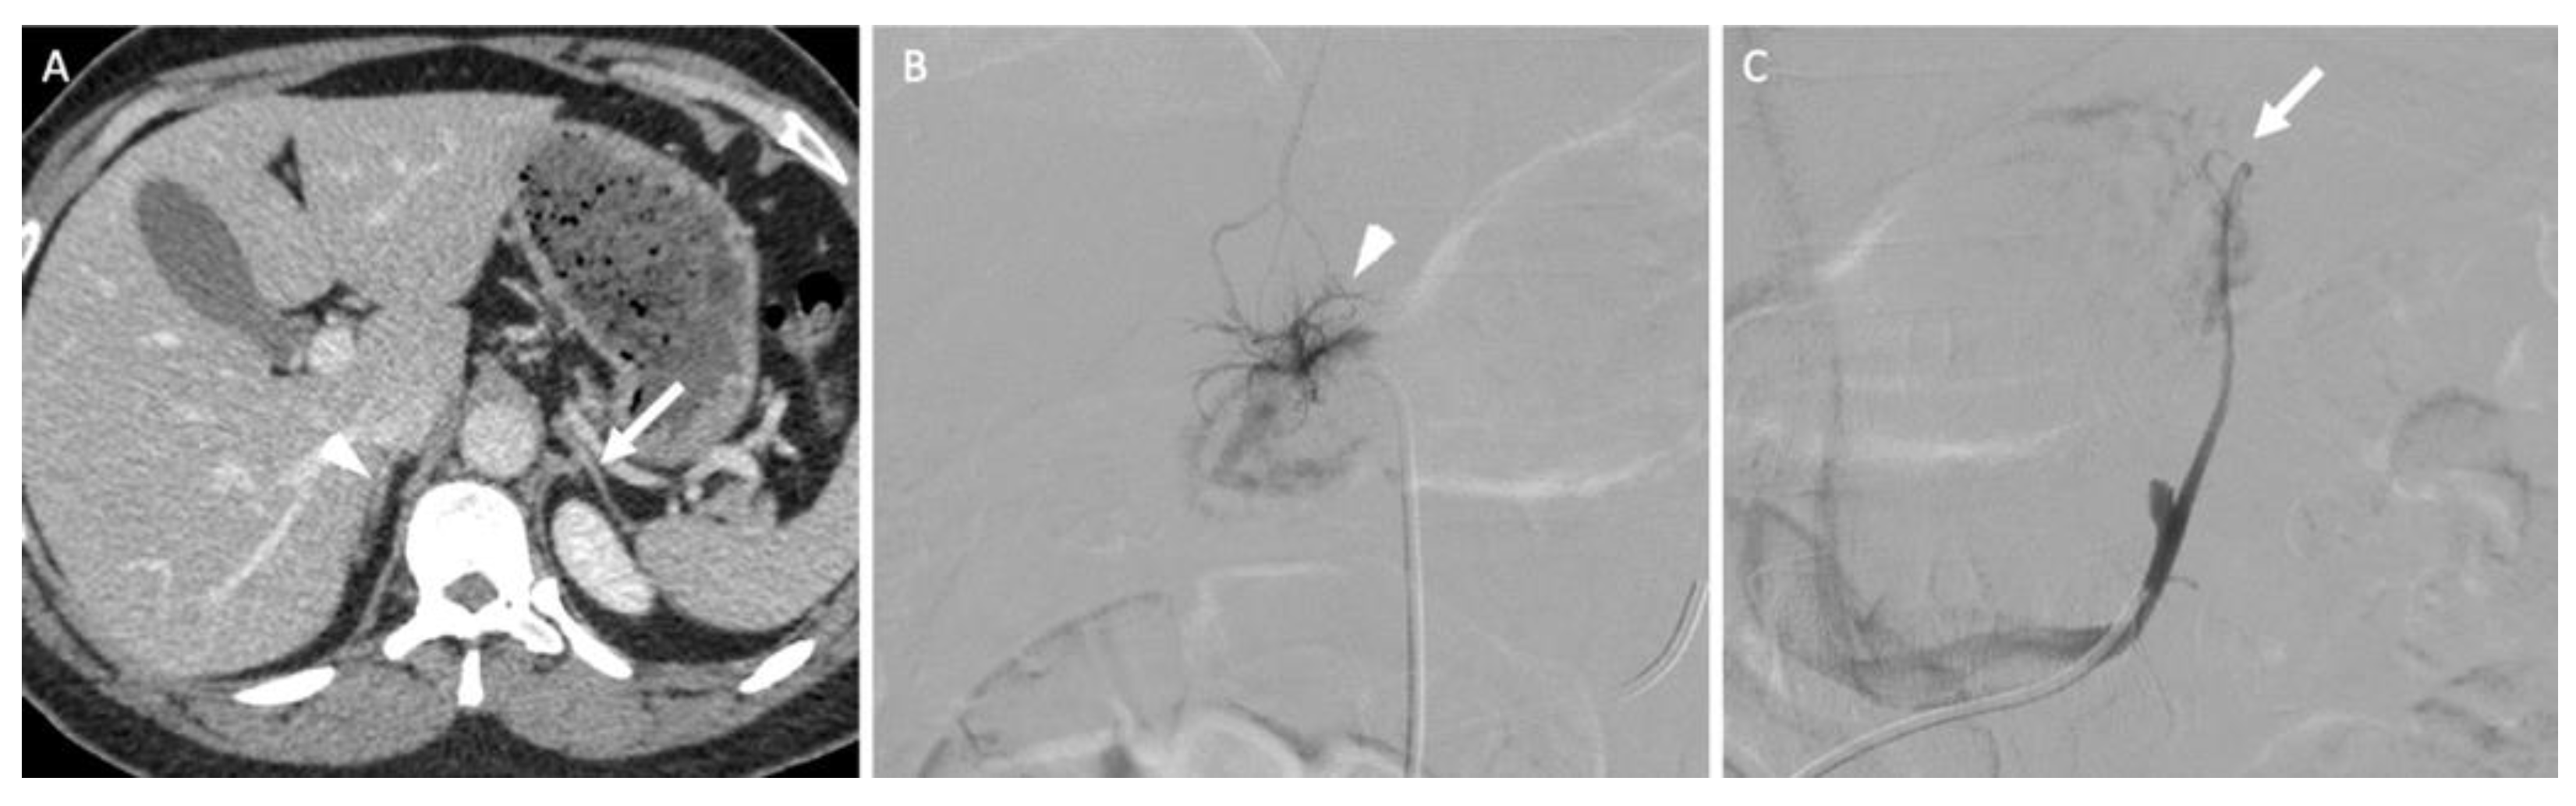

12.1. Adrenal Vein Sampling

- Rossi, G.P.; Auchus, R.J.; Brown, M.; Lenders, J.W.; Naruse, M.; Plouin, P.F.; Satoh, F.; Young, W.F., Jr. An expert consensus statement on use of adrenal vein sampling for the subtyping of primary aldosteronism. Hypertension 2014, 63, 151–160. [Google Scholar] [CrossRef]